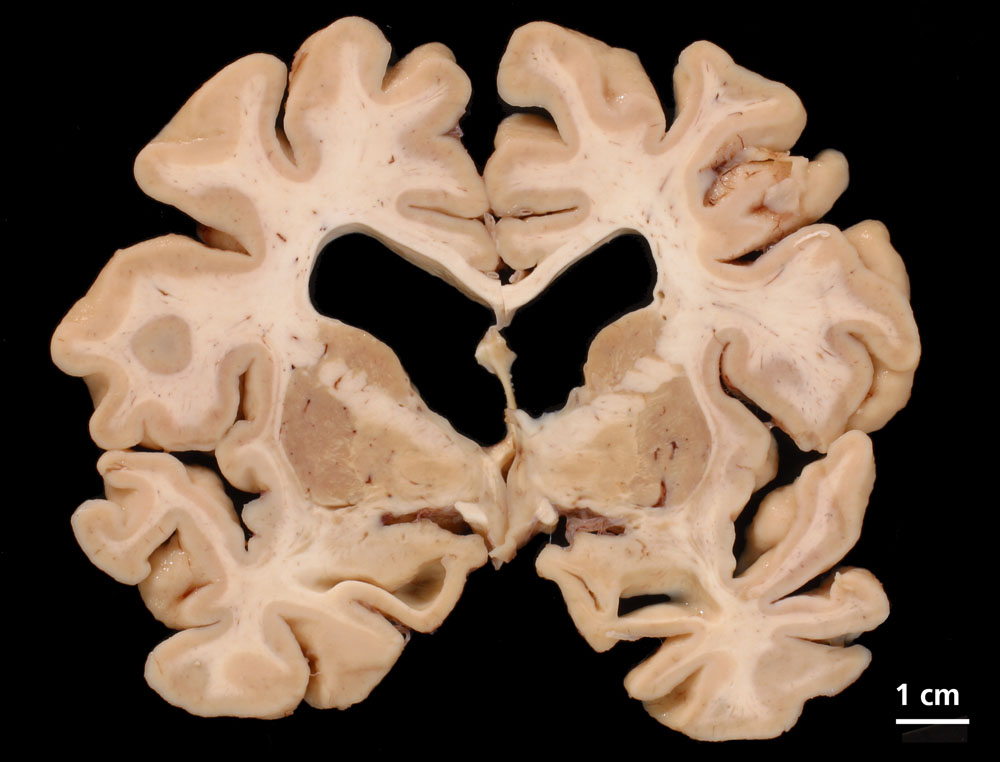

PathoPic – image database / PathoPic ID 9269 - Morbus Alzheimer

Morbus Alzheimer

Die Grosshirnhemisphären stellen sich symmetrisch dar und zeigen eine ausgeprägte kortikale Atrophie. Zusätzlich zeigt der koronare Schnitt eine starke Erweiterung der inneren Liquorräume mit Abrundung der Seitenventrikel. Die Basalganglien sind unauffällig.

Morbus Alzheimer (sicherer Morbus Alzheimer gemäss CERAD, Stadium 2-3 nach Braak und Braak). Demenz mit Lewy-Körpern (DLB, limbischer Typ, laut Newcastle Kriterien). Amyloid-Angiopathie.

Fortgeschrittene dementielle Entwicklung